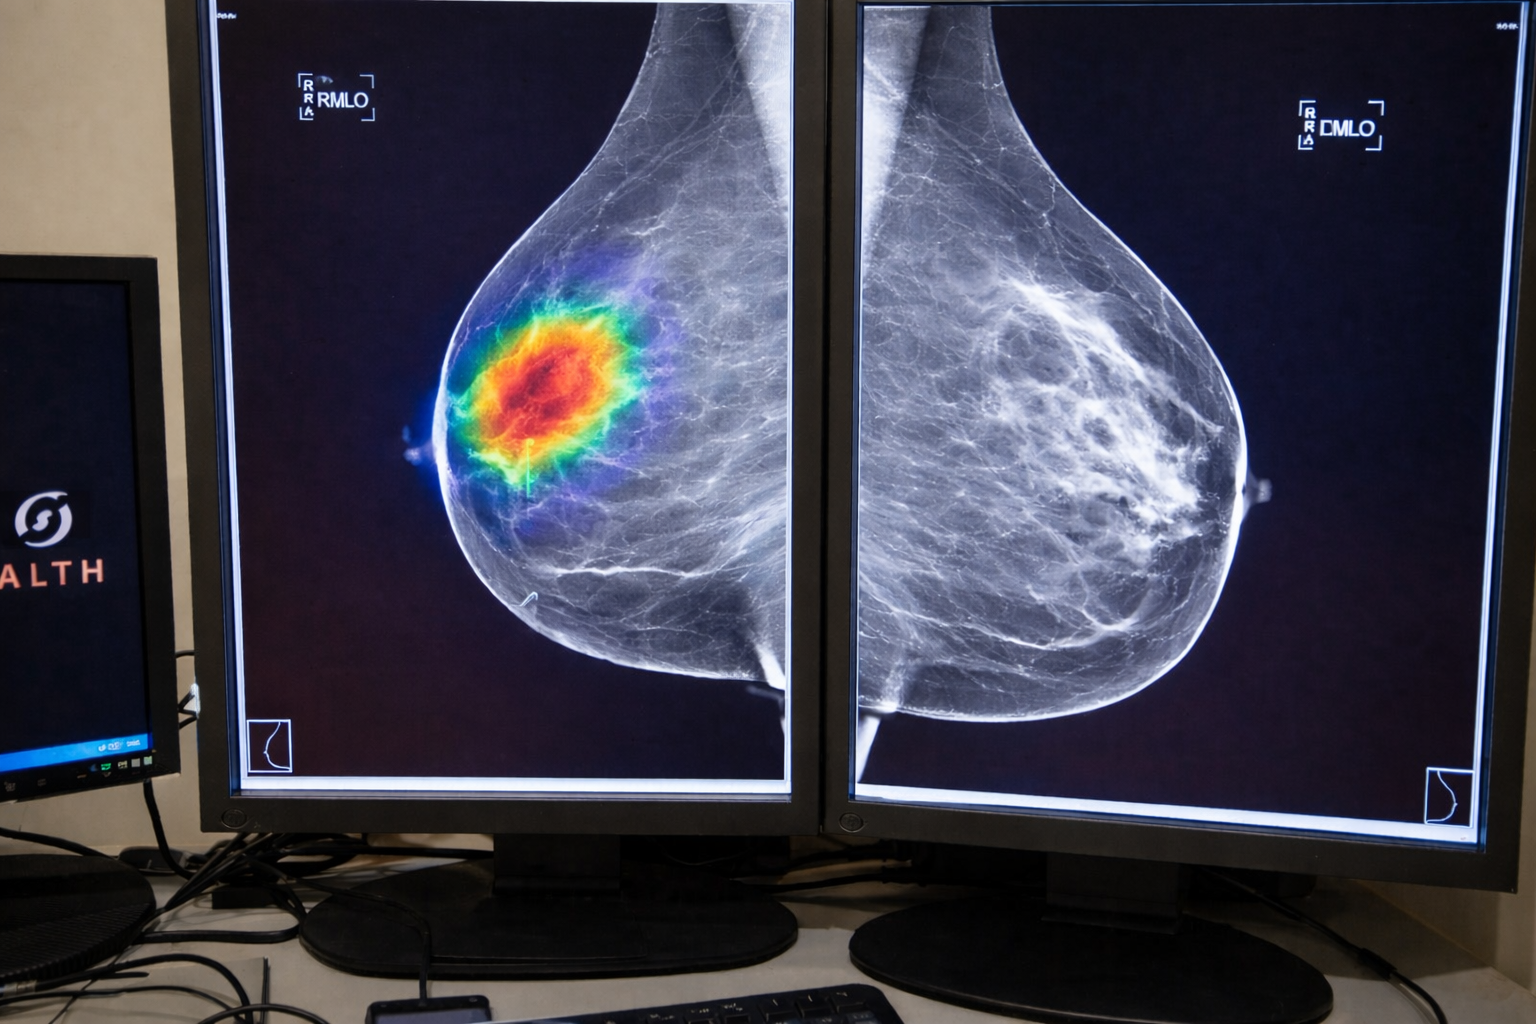

Aprende a evaluar herramientas de IA para la práctica médica

Curso de Evaluación e implementación de herramientas de IA en Salud

Aprende los fundamentos de Inteligencia Artificial y cuál es el proceso adecuado para elegir, evaluar e implementar una herramienta de IA.